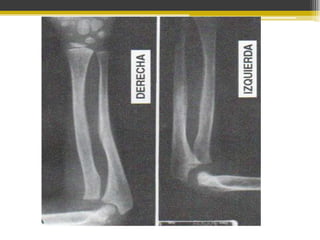

FRACTURA DE MONTEGGIA

CLASIFICACIÓN.

TIPO I O EN EXTENSIÓN.

85% de los casos

cabeza del radio

luxada hacia

delante con

angulación

palmar de la

diafisis del cúbito

TIPO II O POR FLEXIÓN.

10% de los casos.

Cabeza radial

luxada hacia atrás

con angulación

dorsal de la diáfisis

del cubito

fracturada.

DIAGNÓSTICO

Codo inflamado, esquemótico y duele a la presión

La cabeza del radio se palpa anterior, posterior o externo

a su sitio normal.

Radiografías que incluyan codo y muñeca

anteroposteriores y laterales

Tipo I

TRATAMIENTO

Enyesado de 5-7 semanas.

Reducción cerrada.

Tipo II

Tipo III